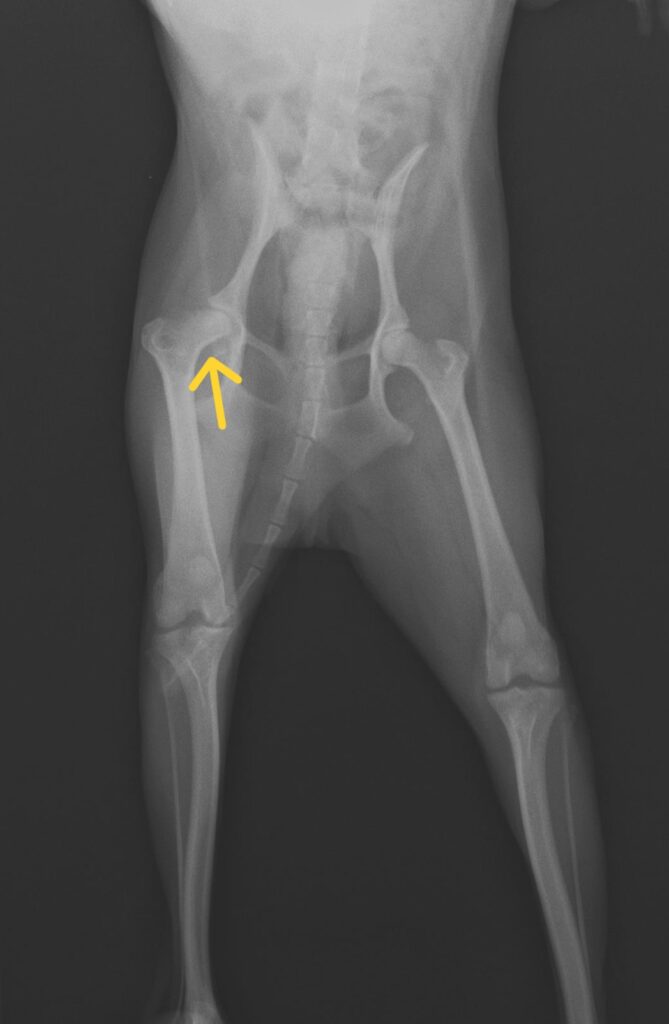

写真上 来院時レントゲン所見 矢印:変形した大腿骨頭

患者は新宿区在住(西東京市以外)1歳のトイプードルで右後肢の跛行を主訴に来院しました。

レントゲン検査でレッグペルテス病が疑われたため外科手術(大腿骨頭切除術)を行いました。